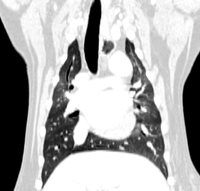

Thorax

- Exploration of the thoracic masses

- Exploration of pleural effusions

- Research of foreign pulmonary bodies (epillets) and exploration of lung abscesses

- Exploration of pneumothorax

- Pulmonary extension assessment in oncology

- Exploration of congenital aortic arch malformations